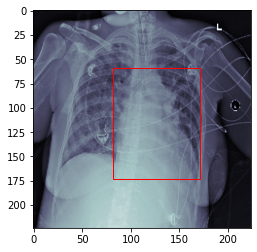

### Test Result on a Sample Image

We will train a model for cardiac detection based on the RSNA Pneumonia Detection Challenge (https://www.kaggle.com/c/rsna-pneumonia-detection-challenge).